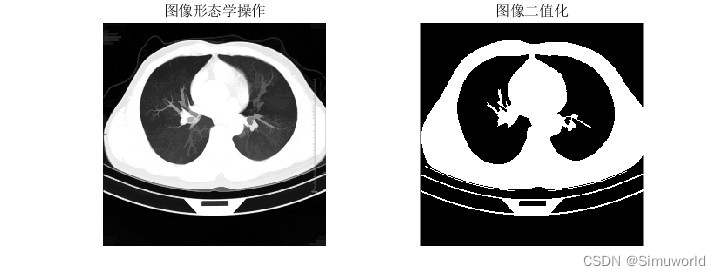

本文介绍了基于分水岭分割算法的肺癌诊断系统,通过MATLAB进行仿真。首先,对CT图像进行预处理,然后运用分水岭算法进行分割,提取肺部区域。接着,通过特征提取和机器学习分类实现肺癌的自动诊断。算法原理包括图像平滑、梯度计算、形态学处理和分水岭变换。